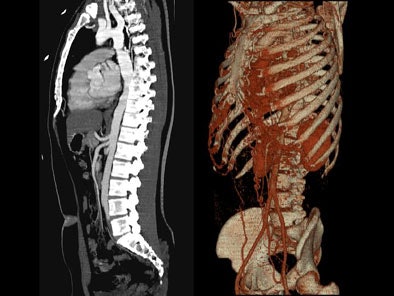

- On sagittal MIP images, the morphology of coarctation along with a captured left subclavian artery was demonstrated. Volume-rendered images showed hypertrophied internal mammary arteries and epigastric arteries. [Figures 3, 4, 5] [Movie 1]

| Figure 4. |